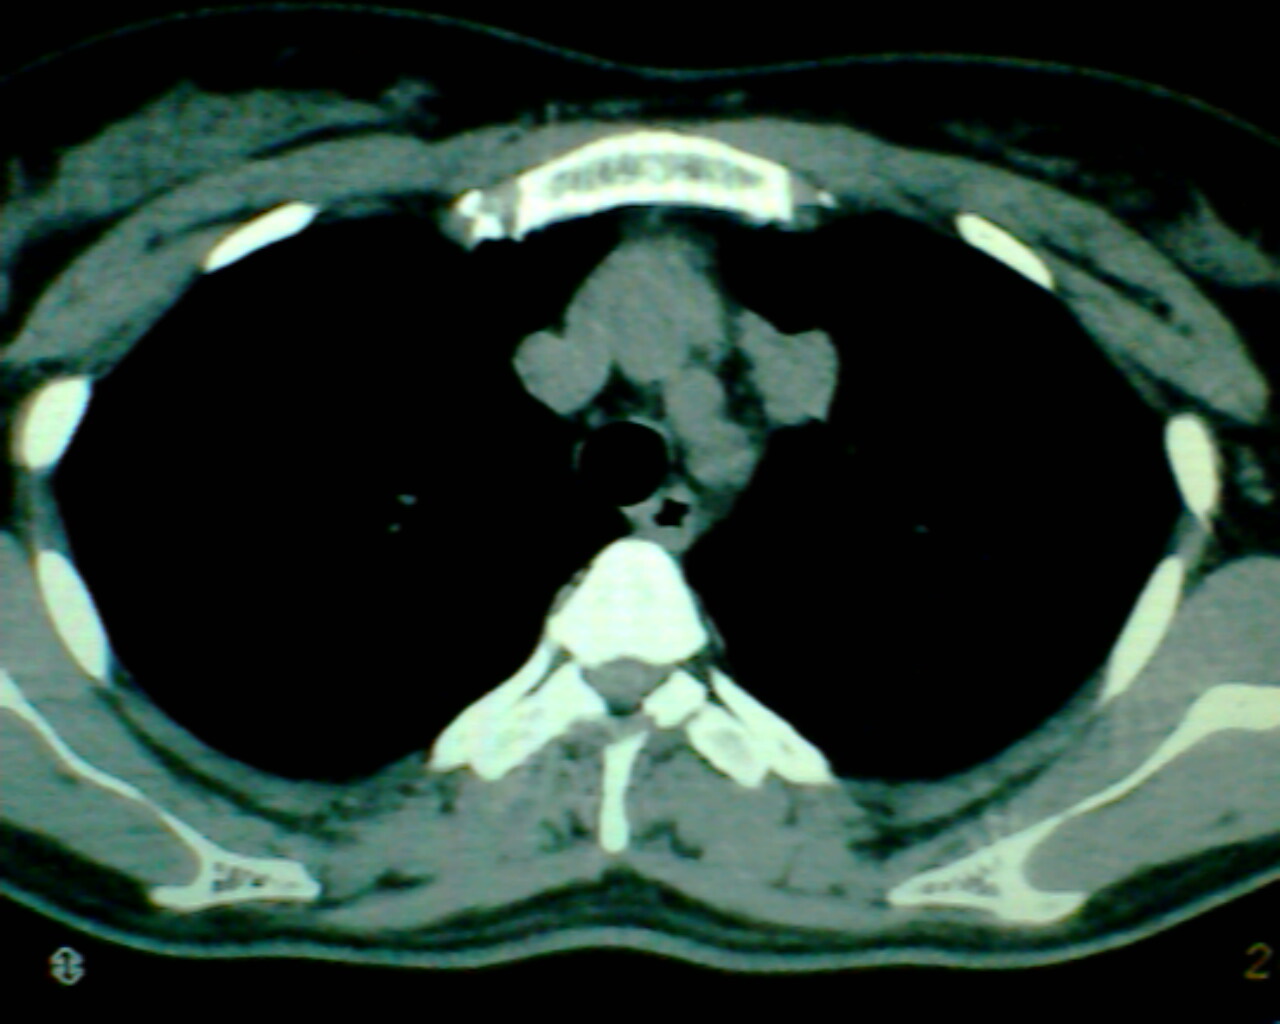

以下是引用狙击手在2007-4-10 22:46:00的发言:[br]考虑:左上纵膈旁型肺癌。理由:1,肿块与纵隔间有分隔;2,肿块呈分叶状;3,肿块突出面圆心在肺内;4,纵隔左移;5,纵隔内器官未见受压征象。